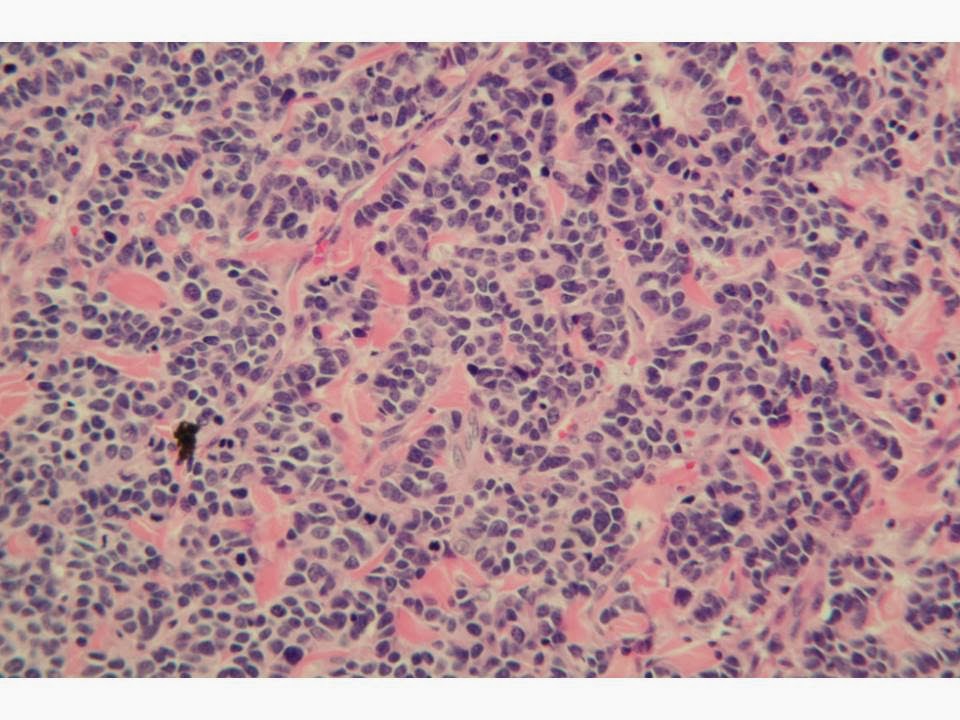

Merkel Cells . Merkel Cell Carcinoma On The Right Eyebrow. | Download Scientific Diagram

Pathology Outlines - Merkel cell carcinoma

Despite the large similarity in phenotype features between mcc tumor cells and physiological merkel cells (mcs), a specialized subpopulation of the epidermis acting as mechanoreceptor of the skin, several points. Mcc begins in these cells. Here, the light touch is a. Merkel cell carcinoma (mcc) is a rare type of skin cancer. They respond to light touch. Merkel cell carcinoma (mcc) is also called neuroendocrine carcinoma of the skin. They are abundant in highly sensitive skin like that of the fingertips in humans. Reconstruction after surgery for skin cancer. It is also known as cutaneous apudoma, primary neuroendocrine carcinoma of the skin, primary small cell carcinoma of the skin. Merkel cells are nondendritic, nonkeratinocytic epithelial cells located primarily in or near the basal layer of the epidermis. Find out more about risk factors, symptoms, tests to. As a result, they are classed as neuroendocrine cells, and mcc, in turn, is sometimes called. These cells cluster and physically contact. The merkel cell is a nondendritic, nonkeratinocytic, clear epithelial cell usually located in or near the basal layer of the epidermis and associated with nerve terminations. Mathew ludgate mbchb, dept of dermatology greenlane hospital auckland, new zealand, 2005. Source for information on merkel cell carcinoma: Learn about merkel cells with free interactive flashcards. Nord gratefully acknowledges neha singh, bs, research scientist, song park, md, and paul nghiem, md, phd, professor & head, university of washington dermatology, for assistance in the preparation of this report. Merkel cell carcinoma is a highly aggressive primary cutaneous neuroendocrine carcinoma primarily affecting elderly and immunosuppressed individuals. Merkel cell carcinoma (mcc) is a primary neuroendocrine carcinoma of the skin. Merkel cell carcinoma tends to travel first to nearby lymph nodes. Even with treatment, merkel cell carcinoma commonly spreads (metastasizes) beyond the skin. Diagnosis requires microscopic evaluation as the clinical appearance is nonspecific and can mimic a variety of benign and malignant skin lesions. The merkel cell is believed to be a mechanoreceptor that mediates the sense of touch. These cells are organized around hair follicles and are believed to act as some type of touch receptors. Merkel cell carcinoma is a rare type of skin cancer that usually starts in areas of skin exposed to the sun. The cancer usually presents as a single reddish or purple lump on a part of the skin that is often exposed to. These cells are thought to function as. Merkel cell carcinoma (mcc) is a rare and aggressive skin cancer occurring in about 3 people per 1,000,000 members of the population. Choose from 23 different sets of flashcards about merkel cells on quizlet. Merkel cells and meissner corpuscles are two of the four types of primary tactile mechanoreceptors in human skin.